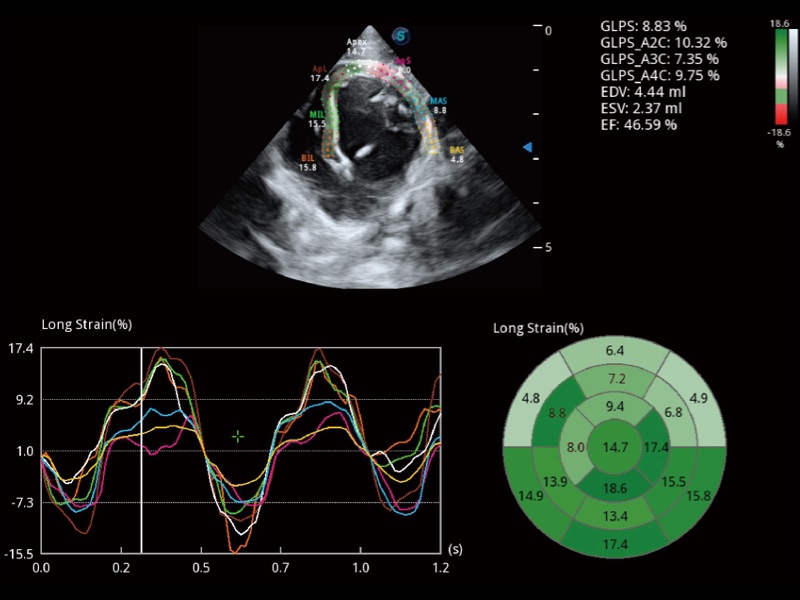

能夠基于左心室壁追蹤和辛普森法,自動計算射血分?jǐn)?shù),支持多個可移動點(diǎn)描跡,與手動測量相比,極大節(jié)省了動物醫(yī)生的時間和精力。